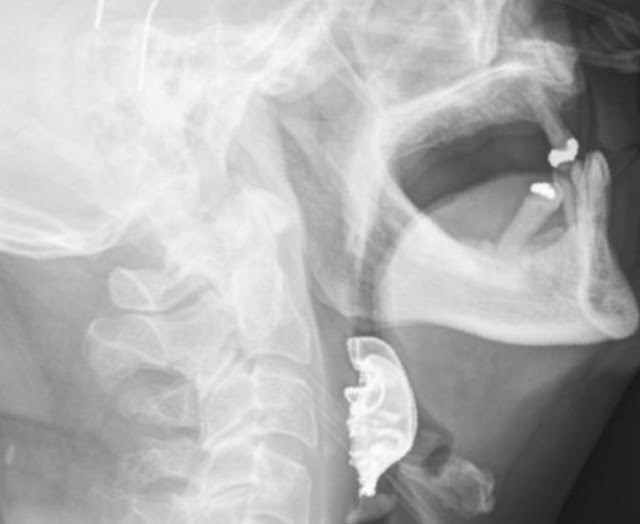

| A obstrução na garganta causou dificuldades para o homem comer, respirar e dormir — Foto: Divulgação/BMJ Case Reports 2019 |

Quando o homem voltou, dois dias depois, a equipe médica examinou mais detalhadamente e encontrou um objeto semicircular sobre as cordas vocais.